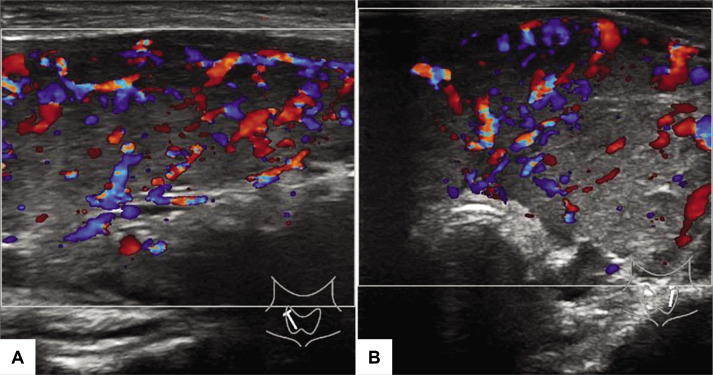

Graves病(GD)表现为甲状腺功能亢进和甲状腺功能减退之间的波动,是一种罕见的现象,对诊断提出了挑战。14岁女性GD,最初被认为患有桥本甲状腺炎,表现为甲状腺肿大和甲状腺功能振荡4年。本病例描述了GD伴甲状腺功能振荡的病例,并强调TSH受体抗体(TRAb)在评估甲状腺功能亢进无Graves眼病患者中的重要性。

Graves' disease (GD) presenting as fluctuations between hyperthyroidism and hypothyroidism is a rare phenomenon and poses a diagnostic challenge. A 14-year-old female with GD, initially thought to have Hashimoto's thyroiditis presented with a goiter and oscillating thyroid function over the course of 4 years. This case depicts a case of GD with oscillating thyroid function and stresses the importance of TSH receptor antibodies (TRAb) in the evaluation of patients with hyperthyroidism without Graves' ophthalmopathy.